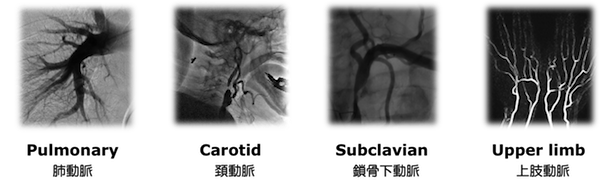

心臓を含め、血液が流れる全身の血管が治療対象です

当院で施行可能なカテーテル治療

- 心筋梗塞、狭心症に対する冠動脈カテーテル治療

- 四肢閉塞性動脈硬化症(間歇性跛行、下肢潰瘍・壊疽)に対するカテーテル治療

- 腎動脈狭窄による腎血管性高血圧、虚血性腎症に対する腎動脈ステント留置術

- 頸動脈狭窄症に対する頸動脈ステント留置術

- 急性動脈閉塞に対するカテーテル血栓吸引療法、カテーテル血栓溶解療法

- 深部静脈血栓症に対する下大静脈フィルター留置術およびフィルター抜去術

- 深部静脈血栓症に対するカテーテル血栓溶解療法およびカテーテル血管形成術

- 中心静脈閉塞、上・下大静脈症候群、腸骨静脈圧迫症候群に対するカテーテル静脈形成術

- 慢性肺血栓塞栓性肺高血圧に対する肺動脈バルーン拡張術

- 大動脈弁狭窄症に対するカテーテル弁形成術(バルーン拡張術)

- 僧房弁狭窄症に対するカテーテル弁形成術(バルーン拡張術)

- 他、血管内異物回収、血管穿孔・小動脈瘤に対するコイル塞栓など